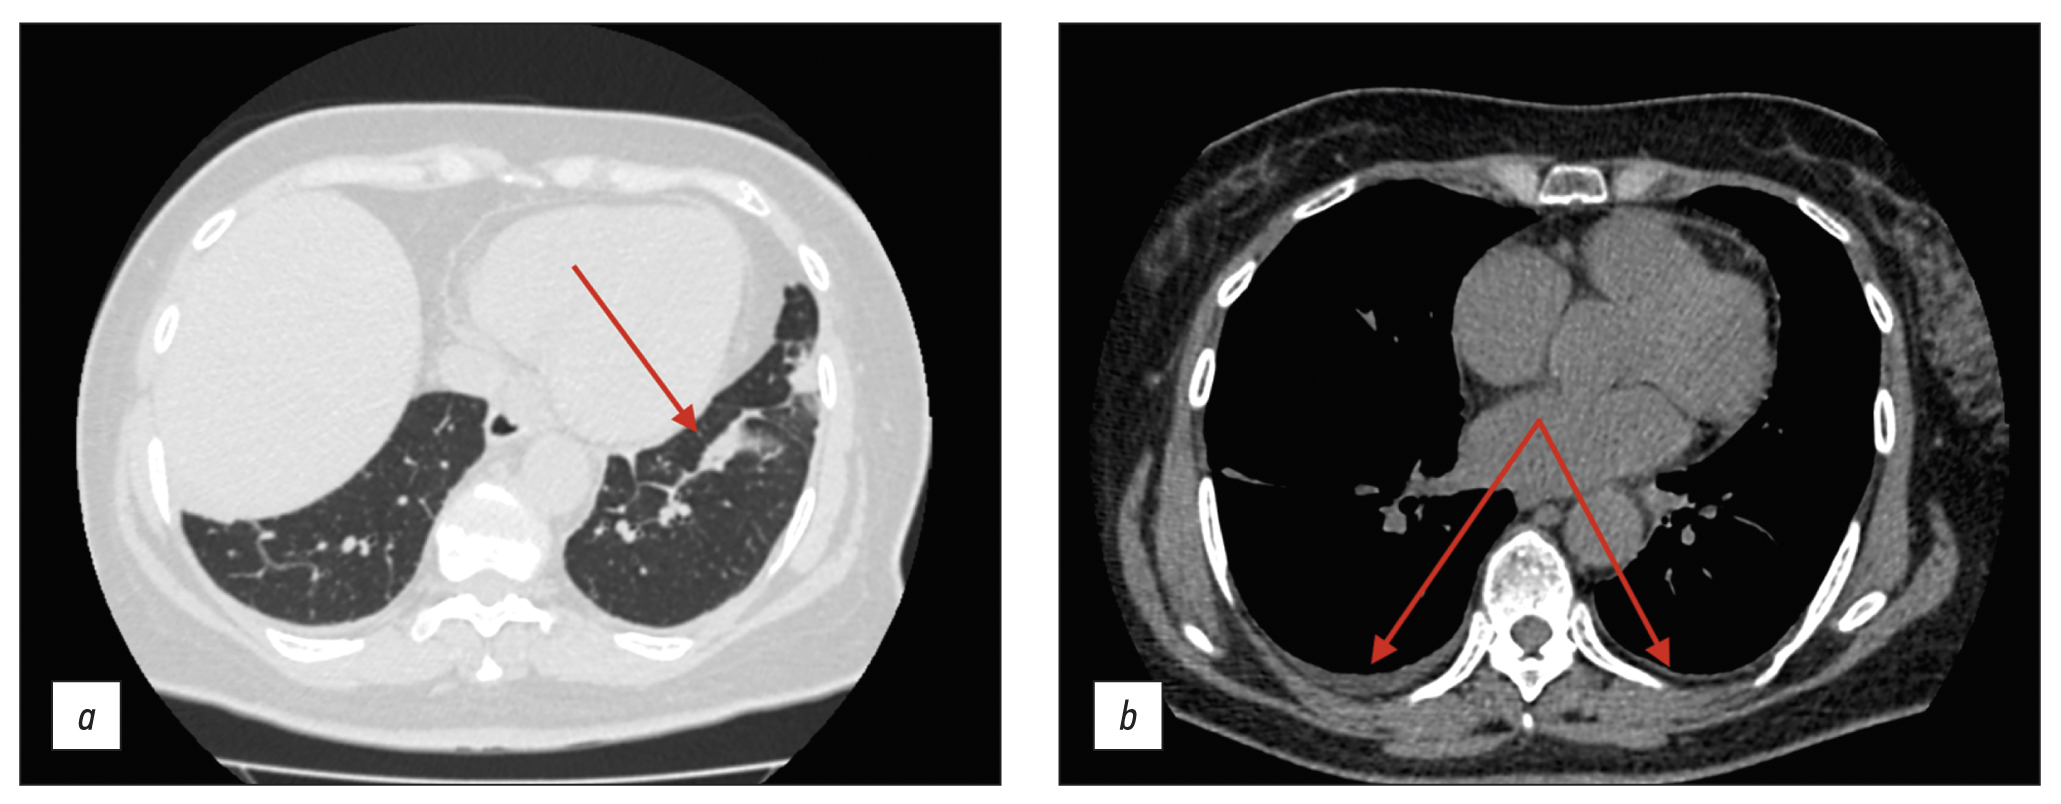

BACKGROUND: Tetralogy of Fallot represents 7–10% of all cases of congenital heart disease, as it occurs in approximately 0.5 per 1,000 live births and is the second most common form of complex congenital heart disease. Advances in diagnosis, surgical techniques, and postoperative treatment have led to an increasing number of patients reaching adulthood, with a dramatic increase in the survival rate to almost 90% at 30 years, thereby creating a need for long-term monitoring of certain anatomic parameters to identify complications in a timely manner. This study aimed to investigate the frequency of computed tomography detected complications after radical correction of Tetralogy of Fallot in pediatric patients.

MATERIALS AND METHODS: A retrospective analysis was conducted on 613 patients with Tetralogy of Fallot from October 2011 to June 2020. The study included a total of 116 patients (69 men and 47 women) who experienced complications after a repair of Tetralogy of Fallot, as identified by computed tomography. At the time of repair of Tetralogy of Fallot, the patient’s average age ranged from 10 to 36 months (mean: 12 months), average body weight was 21 kg, average height was 105.4 cm, and average body surface area was 0.74 m2. The patients’ median age at the time of the computed tomography examination was 17.5 years (age range: 7–36 years).

RESULTS: Among the 116 patients who exhibited complications after an repair of Tetralogy of Fallot, 49 had a pulmonary artery stenosis, 92 had a pulmonary artery branch stenosis (56 of them of the left main pulmonary artery branch, and 36 of them of the right main pulmonary artery branch), 8 had a right ventricular outflow tract stenosis, 32 had a ventricular septal defect, 1 had a shunt thrombosis, 12 had a postoperative deformation of the pulmonary artery, 10 exhibited a marked right ventricular dilatation, 2 had an right ventricular outflow tract aneurysm, and 6 suffered from conduit calcification and stenosis. Moreover, patients with left main pulmonary artery branch stenosis had a 6.5 times greater chance of developing an right main pulmonary artery branch stenosis in (p <0.001).

CONCLUSION: The most frequently computed tomography detected complications after a repair of Tetralogy of Fallot were pulmonary artery stenosis and pulmonary artery branch stenosis. Patients with pulmonary artery stenosis and pulmonary artery branch stenosis exhibit no significant differences in terms of age, anthropometric parameters (height, weight, and body surface area), and gender distribution in the presence or absence of different stenosis types (pulmonary artery, right main pulmonary artery branch, or left main pulmonary artery branch). However, an right main pulmonary artery branch stenosis increases the chances of developing an left main pulmonary artery branch stenosis.